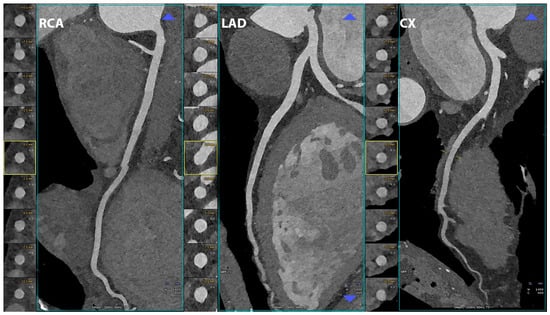

5.1. Coronary Lumen Detection

- Si-Mohamed, S.A.; Boccalini, S.; Lacombe, H.; Diaw, A.; Varasteh, M.; Rodesch, P.-A.; Dessouky, R.; Villien, M.; Tatard-Leitman, V.; Bochaton, T.; et al. Coronary CT Angiography with Photon-counting CT: First-In-Human Results. Radiology 2022, 303, 303–313. [Google Scholar] [CrossRef]

- Channon, K.M.; Newby, D.E.; Nicol, E.D.; Deanfield, J. Cardiovascular computed tomography imaging for coronary artery disease risk: Plaque, flow and fat. Heart 2022, 108, 1510–1515. [Google Scholar] [CrossRef] [PubMed]

- Kruk, M.; Noll, D.; Achenbach, S.; Mintz, G.S.; Pręgowski, J.; Kaczmarska, E.; Kryczka, K.; Pracoń, R.; Dzielińska, Z.; Sleszycka, J.; et al. Impact of coronary artery calcium characteristics on accuracy of CT angiography. JACC Cardiovasc. Imaging 2014, 7, 49–58. [Google Scholar] [CrossRef]

- Li, Z.; Leng, S.; Halaweish, A.F.; Yu, Z.; Yu, L.; Ritman, E.L.; McCollough, C.H. Overcoming calcium blooming and improving the quantification accuracy of percent area luminal stenosis by material decomposition of multi-energy computed tomography datasets. J. Med. Imaging 2020, 7, 053501. [Google Scholar] [CrossRef]